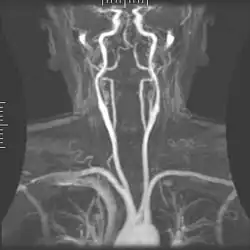

Angiografie

Rezonantele magnetice (MRA) generează imagini ale arterelor pentru a le evalua pentru stenoză (îngustare anormală) sau anevrisme (dilatări ale peretelui vascular, expuse riscului ruperii). MRA este adesea folosit pentru a evalua arterele gâtului și creierului, aorta toracică și abdominală, arterele renale și picioarele (numită "run-off"). O varietate de tehnici pot fi utilizate pentru generarea imaginilor, cum ar fi administrarea unui agent de contrast paramagnetic (gadoliniu) sau folosind o tehnică cunoscută sub denumirea de "îmbunătățire în legătură cu fluxul" (de exemplu, secvențe 2D și 3D de timp de zbor) cea mai mare parte a semnalului de pe o imagine se datorează sângelui care sa mutat recent în acel avion (vezi, de asemenea, RMN FLASH). Tehnicile care implică acumularea de faze (cunoscute sub numele de angiografie cu contrast de fază) pot fi, de asemenea, folosite pentru a genera hărți ale vitezei de curgere cu ușurință și cu precizie. Rezonanța cu rezonanță magnetică (MRV) este o procedură similară utilizată pentru a imagina vene. În această metodă, țesutul este acum excitat inferior, în timp ce semnalul este adunat în planul imediat superior celui de excitație - imaginând astfel sângele venos care sa mutat recent de pe planul excitat.